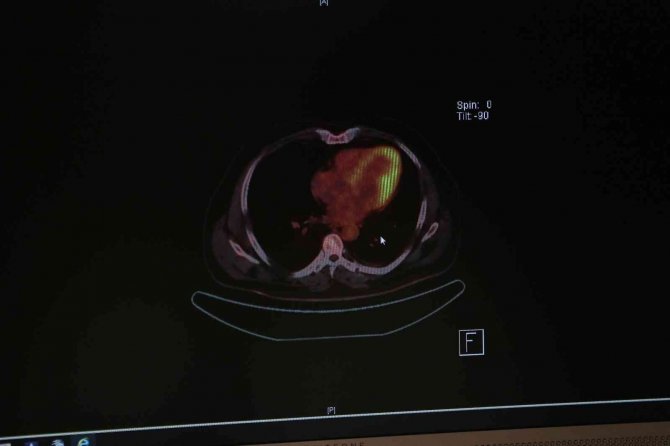

Acıbadem Adana Hastanesi Tıbbi Onkoloji Uzmanı Prof. Dr. Züleyha Çalıkuşu, yaptığı açıklamada, özellikle akciğer kanserine yönelik tarama tetkiklerinin erken tanı şansını artırdığını ve hastalığın tam olarak tedavi edilebilmesini sağladığını kaydetti.

Akciğer kanserinin dünyada en sık görülen kanser türü olduğunu ve ölüme yol açan kanser hastalıkları arasında da ilk sırada yer aldığını belirten Prof. Dr. Çalıkuşu, "Akciğer kanseri erkeklerde en sık ölüme neden olan birinci kanser, kadınlarda ise ikinci kanser türüdür. Dünya genelinde yapılan araştırmalar gösteriyor ki akciğer kanseri genellikle hastalığın metastaz yaptığı dönemde yani diğer organlara sıçradığı evrede teşhis ediliyor. Bu evrede cerrahi şansı yok denecek kadar az oluyor, hastalığın medikal tedavi oranı ise giderek düşüyor" diye konuştu.

"50 yaşın üzerinde bulunan ve en az 20-30 yıldır günde bir paket sigara içenler ya da 10 yıldır iki paket sigara tüketenler, risk grubunda yer alıyor. Bu kişiler için düşük doz bilgisayarlı tomografi çekimi, akciğer kanseri tarama yöntemi olabilir. Erken evrede tanı alan hastalarımız tam tedavi şansına ulaştığı için bu kontroller ihmal edilmemeli. Ne yazık ki koronovirüs pandemisi döneminde hastaneye gelmekten korkan hastaların erken tanı şansı azaldı. Bu sorunu sıklıkla yaşadık. Erken tanı sayesinde kanserin ilk evresinde olan hastalarımız tedavi şansı buldu. Ancak geç tanı alanların tedavisi de gecikti."